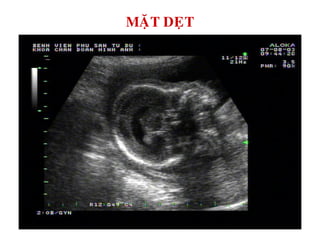

MAËT DEÏT

MAËT DEÏT TREÂN 3D